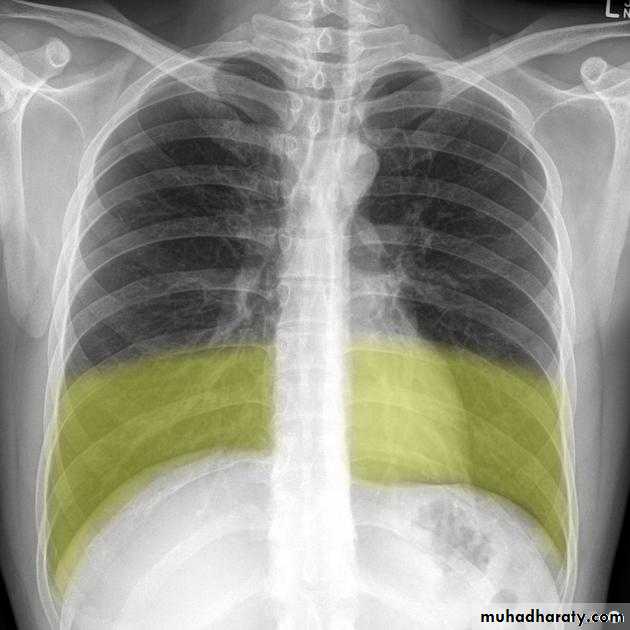

Meniscus sign

Pleural fluid tends to rise higher along its edge producing a meniscus shape medially and laterallyUsually only lateral meniscus can be seen

The meniscus is a good indicator of the presence of a pleural effusion